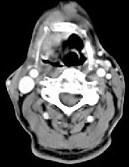

问题 男,63岁,咽喉部不适约1年,近2个月经常咳嗽,痰中带有血丝,CT如图所示,应诊断为()

选项 A.梨状窝癌 B.声门型喉癌 C.声门下型喉癌 D.声门上型喉癌 E.混合型喉癌

答案 D